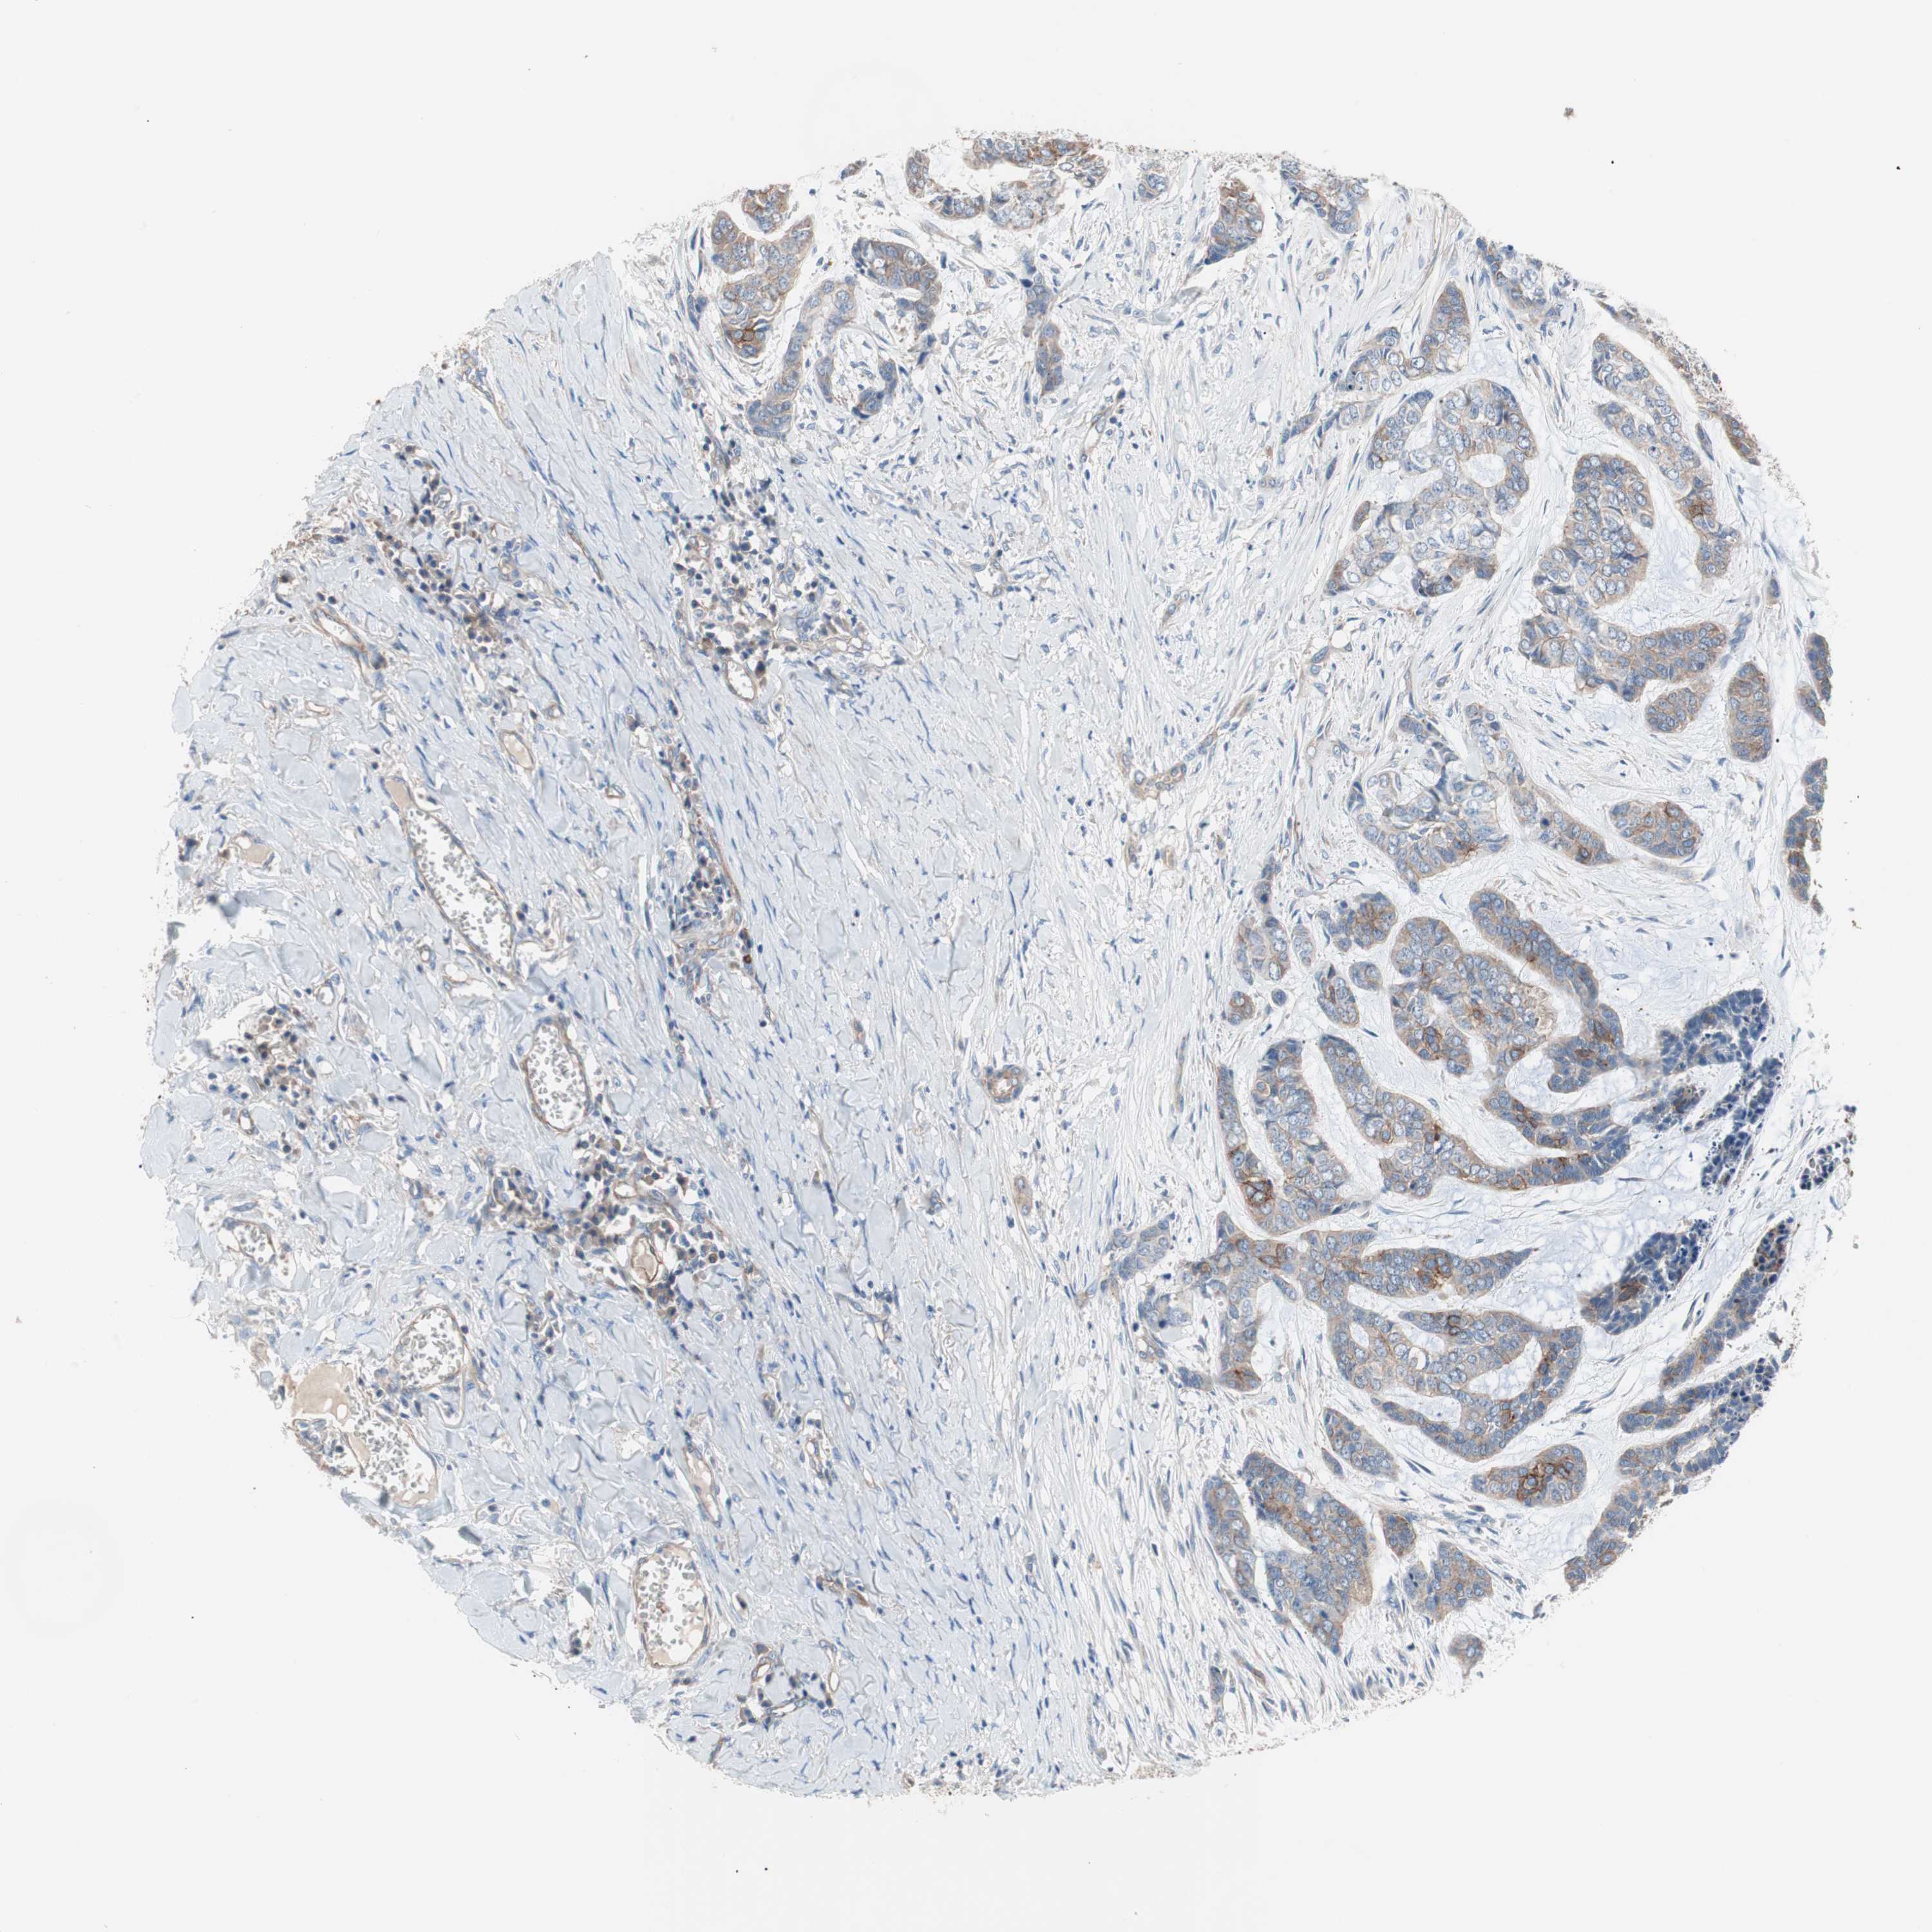

SKIN CANCER - Protein expressioni

A mouse-over function shows sample information and annotation data. Click on an image to view it in a full screen mode. Samples can be filtered based on level of antibody staining by selecting one or several of the following categories: high, medium, low and not detected. The assay and annotation is described here.

Each image is clickable and will lead to virtual microscopy that enables deeper exploration of all samples and also displays staining intensity scores, fraction scores and subcellular localization as well as patient and tissue information for each sample.

Antibody HPA006970

Staining

High

Medium

Low

Not detected

Intensity

Strong

Moderate

Weak

Negative

Quantity

>75%

75%-25%

<25%

None

Location

Nuclear

Cytoplasmic/membranous

Cytoplasmic/membranous,nuclear

Squamous cell carcinoma, NOS

Squamous cell carcinoma, metastatic, NOS

Basal cell carcinoma

Papilloma, NOS